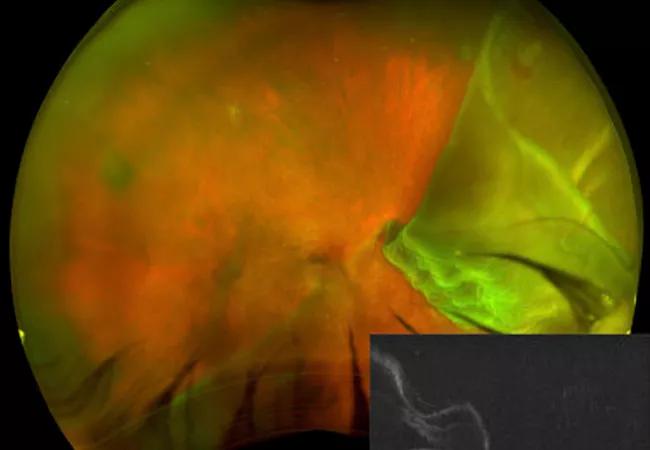

A giant tear of 6 clock hours with a retina that folded on itself

Wide-field fundus photography (Figure A) showed a giant retinal tear of 6 clock hours. In addition, half of the retina folded on itself, and there was bare choroid superotemporally and a horseshoe tear at 1:30 o’clock. We performed vertical spectral-domain optical coherence tomography, which showed detached macula with the foveal center folded over the inferior retina.

At his six-week postoperative visit, the patient’s visual acuity was 20/400 with pinhole. Postoperative fundus photography (Figure B) demonstrated a reattached retina. The vertical optical coherence tomography (OCT) showed silicone oil reflection and ellipsoid zone (arrow) atrophy (between arrowheads) in the foveal center.

In the case presented here, the OCT image shows the foveal pit that is not only detached, but also folded over the inferior retina in a “tidal wave” configuration.